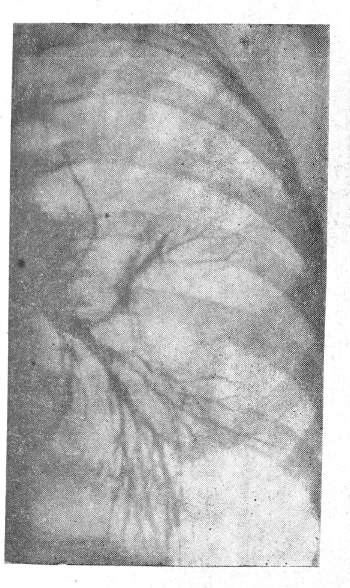

У Ш., 59 лет, при обычном рентгеновском исследовании отмечена зубчатость большой кривизны. Пальпаторно признаков нарушения эластичности выявить не удалось, и зубчатость была объяснена петлистостью утолщенных складок слизистой (рис. 1, см. вклейку). Однако у рентгенолога в оценке состояния большой кривизны возникли сомнения. Было решено вызвать больную для повторного просвечивания. В результате исследования, проведенного двуконтрастным методом, там, где обратила на себя внимание зубчатость большой кривизны, рисунок рельефа остался стабильным, в то время как во всех других отделах складки сгладились. Между обрывами плавных очертаний большой кривизны стенка желудка оказалась деформированной, ригидной (рис. 2). Заключение: раковая опухоль желудка. Больная госпитализирована. При гастроскопии на передней стенке и на большой кривизне желудка в нижней трети его тела выявлена плоская опухоль с четко очерченным валикообразным бугристым краем и изъязвлением в центре (рис. 3). При пробной лапаротомии найдена раковая опухоль 4X10 см, располагающаяся в области тела желудка. Имеются метастазы.

Рис.1. Рентгенограмма больной Ш. На прицельном снимке желудка определяется зубчатость большой кривизны. Палъпаторно признаков нарушения эластичности

здесь уловить не удалось.